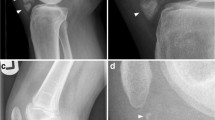

Hereditary multiple exostoses (HME) is a complex musculoskeletal pediatric disorder characterized by osteochondromas that form next to the growth plates of many skeletal elements, including long bones, ribs, and vertebrae. Due to its intricacies and unresolved issues, HME continues to pose major challenges to both clinicians and biomedical researchers. The purpose of this review is to describe and analyze recent advances in this field and point to possible targets and strategies for future biologically based therapeutic intervention.

Most HME cases are linked to loss-of-function mutations in EXT1 or EXT2 that encode glycosyltransferases responsible for heparan sulfate (HS) synthesis, leading to HS deficiency. Recent genomic inquiries have extended those findings but have yet to provide a definitive genotype-phenotype correlation. Clinical studies emphasize that in addition to the well-known skeletal problems caused by osteochondromas, HME patients can experience, and suffer from, other symptoms and health complications such as chronic pain and nerve impingement. Laboratory work has produced novel insights into alterations in cellular and molecular mechanisms instigated by HS deficiency and subtending onset and growth of osteochondroma and how such changes could be targeted toward therapeutic ends.

Clement ND, Duckworth AD, Baker AD, Porter DE. Skeletal growth patterns in hereditary multiple exostoses: a natural history. J Pediatr Orthop. 2012;B21:150–4.

Clement ND, Porter DE. Hereditary multiple exostoses: anatomical distribution and burden of exostoses is dependent upon genotype and gender. Scottish Med J. 2014;59:34–44.

Porter DE, Benson MK, Hosney GA. The hip in hereditary multiple exostoses. J Bone Joint Surg Br. 2001;83:988–95.

Wang YZ, Park K-W, Oh C-S, Ahn Y-S, Kang Q-L, Jung ST, et al. Developmental pattern of the hip in patients with hereditary multiple exostoses. BMC Musculoskelet Disord. 2015;16:54.